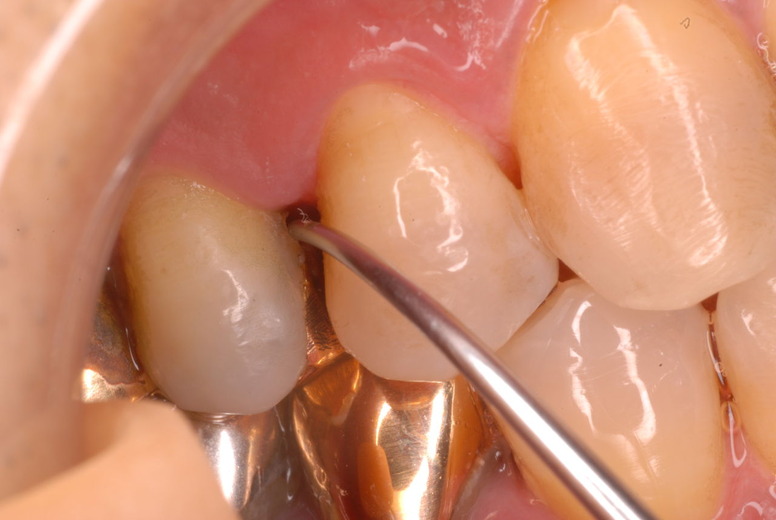

色々不満な入れ歯です。

発音や見える金属が気になるようです。

ご自分でやられても歯茎から血が出ないと話をされていましたが、私がブラシを当てると悲惨な状態であることがわかりました。